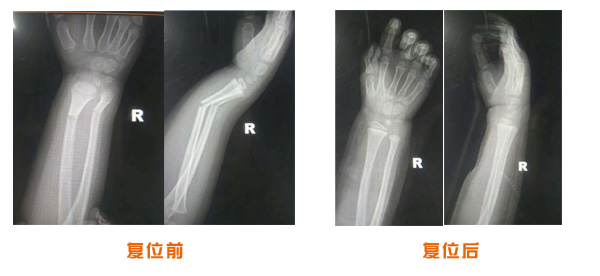

肥城市安駕莊梁氏骨科醫(yī)院是一所以梁氏手法正骨配合膏藥為特色的現代化??漆t(yī)院。

梁氏骨科術始創(chuàng)于清雍正年間,歷經八代,至今已有三百年歷史。據1929年泰安縣志載“梁瑞圖先生,字增生,號蓮峰,安駕莊人,精岐黃并發(fā)明接骨,凡跌打車凡跌打車軋皮不破而碎骨者......【詳細】 |